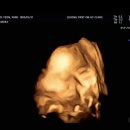

세종제일산부인과의원 세종특별자치시 한누리대로 2265 6층 39주 3일차에 유도분만을 잡았다 원장님은 1-2주 정도 빨리 잡아도 된다 했지만 최대한 품을 수 있을때 까지는 버티고 싶었다  아침에 제육을 든든히 먹고 출발했다 ㅎㅎ  병원 도착해서 의사선생님 면담하구 최종 초음파 보는데 역시나 얼굴을 안보여줬다...